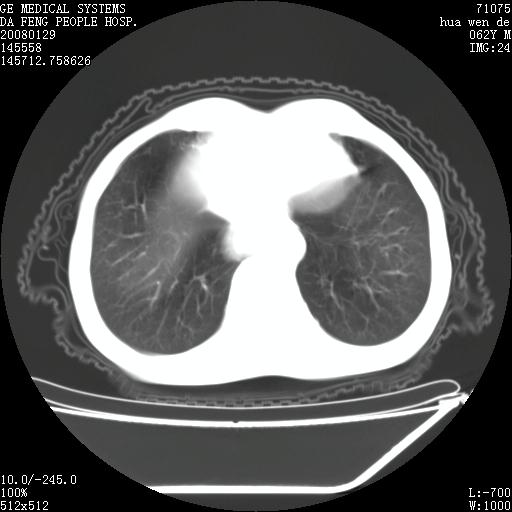

男性,67岁。作肺部检查时发现

考虑:胸腔胃并支气管瘘(并发肺炎,肺脓肿形成)。

理由:1、右上肺内病灶,空洞形成,有液平。

2、肺内多处炎症。

考虑:胸腔胃并支气管瘘(并发吸入肺炎,肺脓肿形成)。

3、前段肺内炎症,支气管引流通畅,与肿块无关系。

1.整个食管扩张,未见明显占位性病变,贲门区亦未见明显占位病变,考虑:贲门失驰缓症;

2.右上肺病变边缘可见毛刺,囊壁厚度不均匀,周围境界较清楚,未见炎性渗出性影,右上肺外带可见片状影,边缘不清,考虑:肺癌伴空洞形成、右上肺炎。

食管全程扩张,壁均匀不厚,喷门失弛缓症

右上肺空洞可见液平,临近肺野磨玻璃密度,考虑1.结核2.脓肿